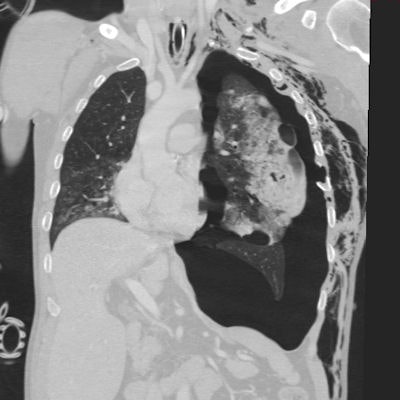

The great strength of multidetector-row CT (MDCT) is its high speed and high geometric resolution in any plane, noted Dr. Hynek Mirka, PhD, deputy head of research and development in the department of imaging methods at Charles University and University Hospital in Pilsen, Czech Republic. It makes it possible to view large parts of the body with minimal motion artifacts and to create accurate multiplanar and 3D reformations, which boosts the accuracy of the diagnosis significantly. Because of these advantages, MDCT has become the first-choice method in high-energy traumas.

In the article, Mirka and colleagues summarize the position of MDCT in the diagnostic algorithm of chest injuries, technical aspects of the examination, and imaging findings in traumas of the individual chest compartments. They explain how detailed information can be acquired in a short acquisition time, and multiplanar and 3D reformatting make the diagnosis significantly more accurate.

Injury to the lung parenchyma includes pulmonary contusion, laceration, torsion, and herniation. These conditions can be complicated by atelectasis, aspiration pneumonia, or acute respiratory distress syndrome. Lung trauma is seldom a reason for surgical treatment, according to the authors. This is indicated in cases of injury of the major blood vessels, signs of active bleeding, large hematomas, or hemodynamic instability in the context of pulmonary involvement.